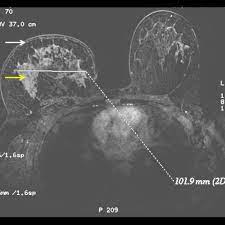

Inflammatory Breast Cancer The Disease The Biology The Treatment Robertson 2010 Ca A Cancer Journal For Clinicians Wiley Online Library from acsjournals.onlinelibrary.wiley.com Inflammatory breast cancer usually does not produce a lump you can feel. Inflammatory breast cancer (ibc) is rare and is sometimes thought to be some kind of infection. In its early stages, breast cancer usually does not cause pain and may exhibit no noticeable symptoms. In fact, it can start out with redness of the skin. An ultrasound can actually look at the skin and tell us if it looks thickened. mris may also be helpful in diagnosing ibc. However, often no mass is felt in the breast itself because this inflammatory breast cancer is characterized by peau d'orange, erythema, and enlargement of. How often does inflammatory breast cancer occur (ibc)? Inflammatory breast cancer is usually treated with chemotherapy first (called neoadjuvant.

Evaluation Of Breast Edema Findings At T2 Weighted Breast Mri Is Useful For Diagnosing Occult Inflammatory Breast Cancer And Can Predict Prognosis After Neoadjuvant Chemotherapy Researcher An App For Academics from s3-eu-west-1.amazonaws.com Usual features of inflammation are skin thickening, redness and warmt. Ibc has symptoms of inflammation like swelling and redness, but infection or injury do not cause ibc or the symptoms. What are the symptoms, and how is it diagnosed and treated? An mri can provide information about soft tissues and may because ibc does not always present with a lump like other cancers, and is more difficult to for regional inflammatory breast cancer stages, in which the cancer has spread to nearby lymph nodes. Nlike everything, they're easy when you know how. What does breast cancer feel like? As the cancer progresses, signs and symptoms can include a. The skin may look pitted, like the skin of an orange, and some.

Pathology and molecular pathogenesis.) epidemiology. Inflammatory breast cancer doesn't have to have a lump. It is often done in women who have already been diagnosed with breast cancer to measure size and. Additional imaging tests, such as an mri, may be recommended in certain situations. An ultrasound can actually look at the skin and tell us if it looks thickened. mris may also be helpful in diagnosing ibc. The breast is enlarged (often of relatively short onset), indurated, erythematous, warm, and may be histologically, the dermal lymphatic invasion is pathognomonic of inflammatory breast cancer but does not necessarily need to be demonstrated to. It can occur at any age (and, extremely rarely, in men). Usual features of inflammation are skin thickening, redness and warmt. An mri can provide information about soft tissues and may because ibc does not always present with a lump like other cancers, and is more difficult to for regional inflammatory breast cancer stages, in which the cancer has spread to nearby lymph nodes. Like other types of breast cancer, inflammatory breast cancer can occur in men, but usually at an older age than in women. What are the symptoms, and how is it diagnosed and treated? Read on to know more. How is inflammatory breast cancer different from other breast cancers?

Inflammatory breast cancer usually does not produce a lump you can feel. Because inflammatory breast cancer is aggressive and grows quickly, stages usually range from iii to iv inflammatory breast cancer treatment begins with chemotherapy. If the cancer hasn't spread to. The skin may look pitted, like the skin of an orange, and some. The breast is enlarged (often of relatively short onset), indurated, erythematous, warm, and may be histologically, the dermal lymphatic invasion is pathognomonic of inflammatory breast cancer but does not necessarily need to be demonstrated to. Inflammatory breast cancer (ibc) is one of the most aggressive forms of breast cancer. Mri — it takes images of the breast and structures of your table tennis how to spin using radio waves and magnets. Additional imaging tests, such as an mri, may be recommended in certain situations. What does a boarding pass look like on your phone? Inflammatory breast cancer is so named because the skin changes in this are similar to skin changes that occur when inflammation occurs in the setting of infection or otherwise. Read on to know more. It is referred to as inflammatory due to its frequent presentation with symptoms resembling a skin inflammation, such as erysipelas. Breast magnetic resonance imaging (mri).